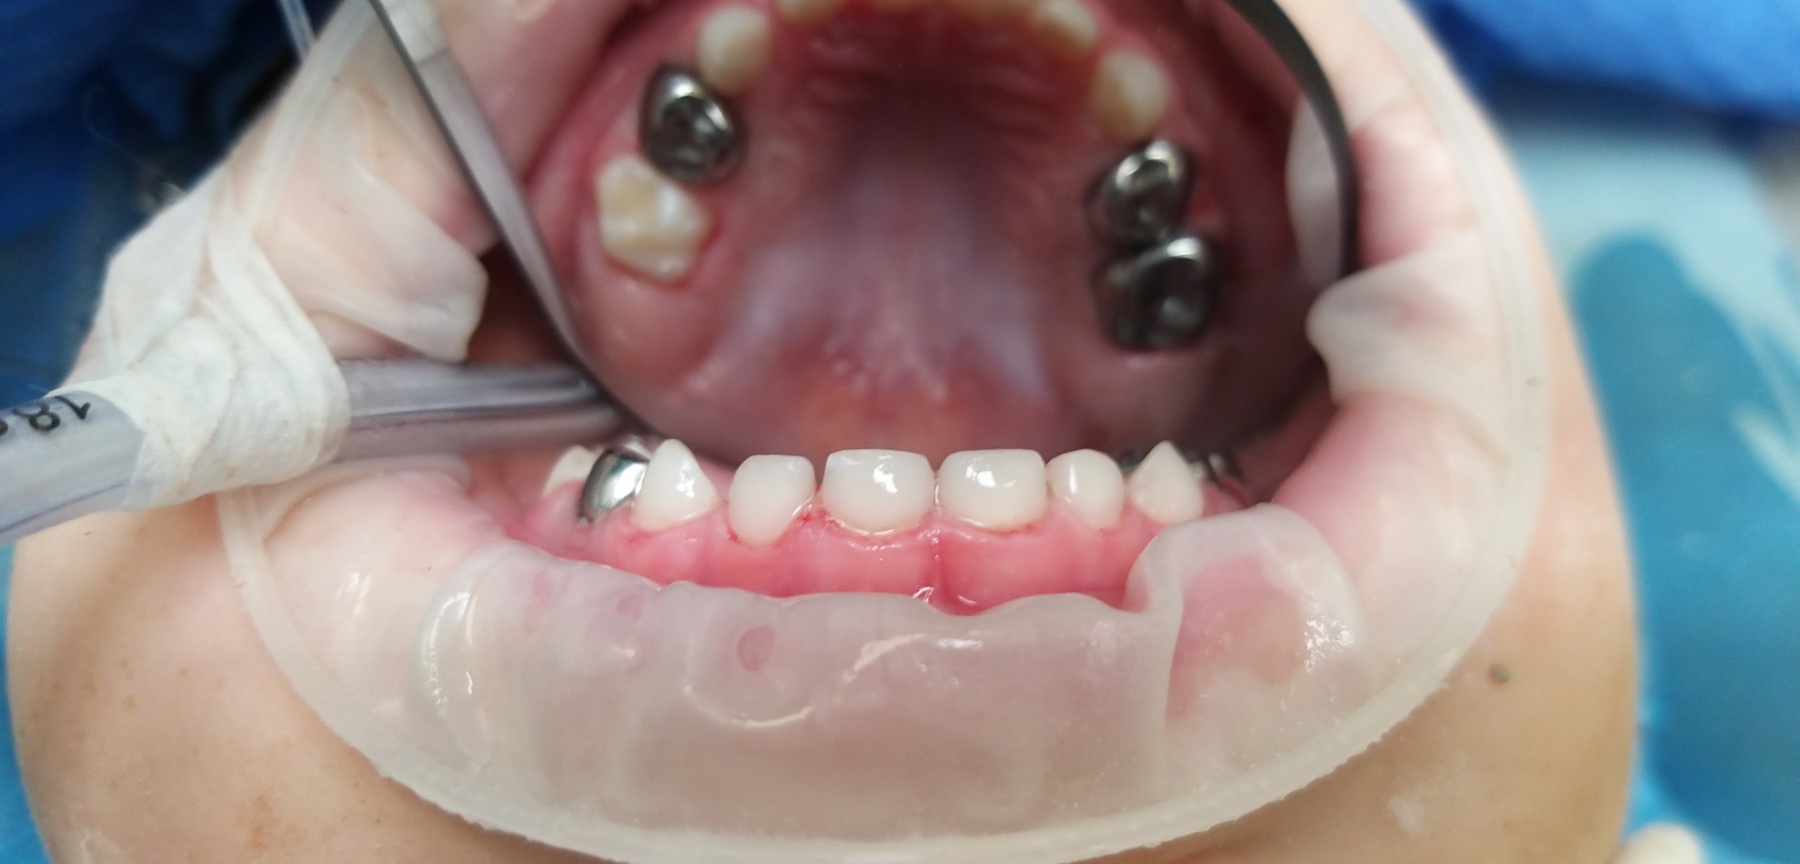

Лікар стоматолог - терапевт